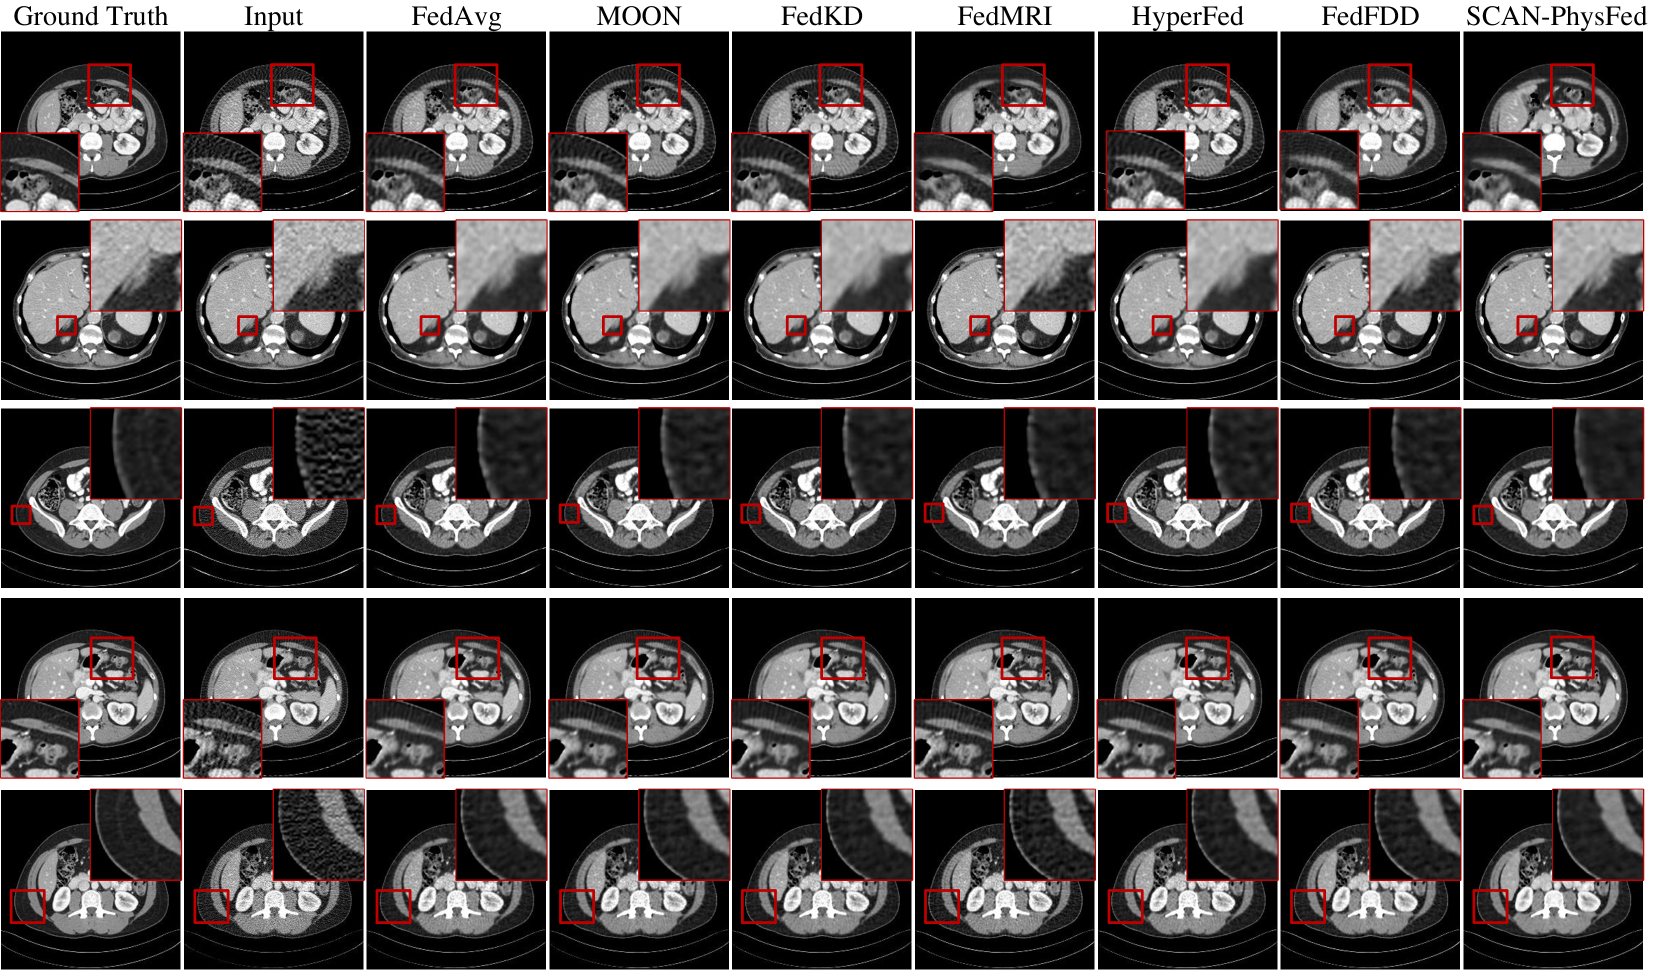

Refer to caption

Figure 4: Qualitative results of six selected comparison methods and our method across different clients using the classical convolutional-based LDCT imaging network. Rows one to five represent Clients #2, #3, #5, #6, and #7, respectively. The display window for the first row is [-1024, 200] HU, while for the other rows, it is [-160, 240] HU.

Representative slices produced by different methods are shown in Figure 4. We compared the top three methods from both generic and personalized FL approaches. Representative clients were selected based on different radiology reduction strategies: sparse-view (Clients #2 and #6) and low-dose (Clients #3, #5, and #7). It can be observed that other methods exhibit noticeable noise or artifacts in sparse-view protocols, and fail to preserve details in low-dose protocols. However, ours effectively reduces noise and artifacts in the sparse-view protocols while preserving fine details in low-dose protocols. SCAN-PhysFed achieves strong performance across slices from different body parts, benefiting from the introduction of anatomy prior. Both quantitative and qualitative results demonstrate the effectiveness of incorporating physical information.